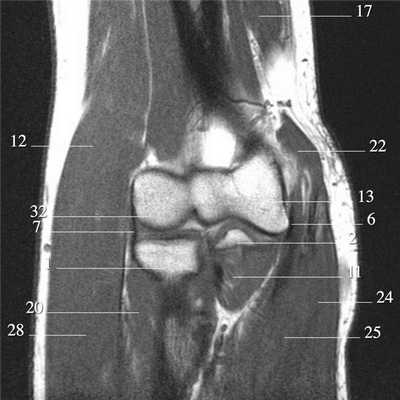

Локтевой сустав (МРТ анатомия)

Описание исследования 1 - головка лучевой кости 2 - венечный отросток локтевой кости 3 - локтевая кость 4 - локтевой отросток 5 - сухожилие трехглавой мышцы 6 - медиальная коллатеральная связка локтевого сустава 7 - лучевая коллатеральная связка локтевого сустава 8 - латеральная коллатеральная связка 9 - латеральный надмыщелок плечевой кости 10 - сухожилие двуглавой мышцы плеча 11 - плечевая мышца 12 - длинный лучевой разгибатель запястья 13 - блок плечевой кости 14 - локтевая мышца 15 - глубокий сгибатель пальцев 16 - локтевой сгибатель запястья 17 - трехглавая мышца 18 - кольцевидная связка лучевой кости 19 - двуглавая мышца плеча 20 - супинатор 21 - плечелучевая мышца 22 - круглый пронатор 23 - разгибатель пальцев 24 - лучевой сгибатель запястья 25 - поверхностный сгибатель пальцев 26 - локтевой нерв 27 - локтевой сгибатель запястья 28 - короткий лучевой разгибатель запястья 29 - общее сухожилие разгибателей 30 - общее сухожилие сгибателей и круглого пронатора 31 - бугристость лучевой кости 32 - головка плечевой кости 33 - медиальный надмыщелок плечевой кости 34 - гребень супинатора 35 - трапециевидная связка (lacertus fibrosus) 36 - наружная головка трехглавой мышцы плеча 37 - длинная головка трехглавой мышцы плеча 38 - медиальная головка трехглавой мышцы плеча 39 - общее сухожилие сгибателей